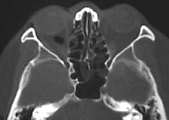

男45y3小时前被打伤眼部,无鼻出血,hrct示右眼眶内壁眼内直肌内侧有积气,可不可以定为眶内壁骨折???

可以考虑眶内壁骨折,能不能缩小显视野,将图像放大观察,第一幅图像气体影处有一小致密结节,请上传邻近层面的图像。

右眼眶内壁与眼内直肌间可见积气,应该可以认为是眶内壁骨折的间接征象,筛骨纸板很薄,容易发生骨折,典型的骨折较难看到。

眶内壁有缺埙,内直肌外气体影,眶内壁骨折。